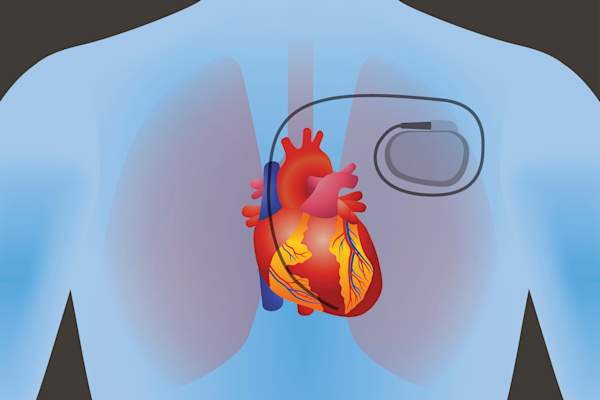

当需要设备来控制心脏节律时

当心脏肌肉需要反复,甚至不断,提醒按顺序打,和药物是不够的,不同的设备可以帮助来代替。两种类型的设备,心脏起搏器和植入式心脏除颤器(ICD)的,给予卫生专业人员来控制病人的心脏率和点播抽水能力的能力 - 也就是当心律失常发生。

设备合同。

起搏器可能是临时的,也可能是永久性的,内部或外部的电池发电机和引线(导线)在皮下。这些导线发送电子信息,使心肌有规律地收缩。相反,除颤器同时提供低冲击重置心律不齐和更大的冲击来对付危险的室性心律失常。像心脏起搏器,心脏除颤器使用电池和导线进入心脏,但设备在胸部或腹部皮肤下放置。